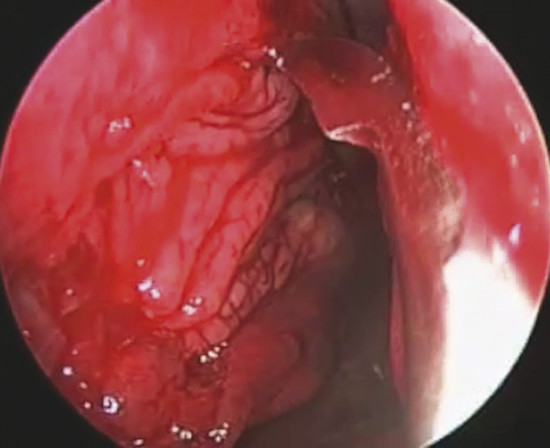

The perforation margins are then bilaterally trimmed and widely detached all around the perforation from the underlying cartilage or bone by a sickle knife to achieve a “refreshening of the edge” (Fig. 19‑1). It is important to elevate bilaterally an area of mucoperiosteum or mucoperichondrium of at least 1 cm all around the perforation.